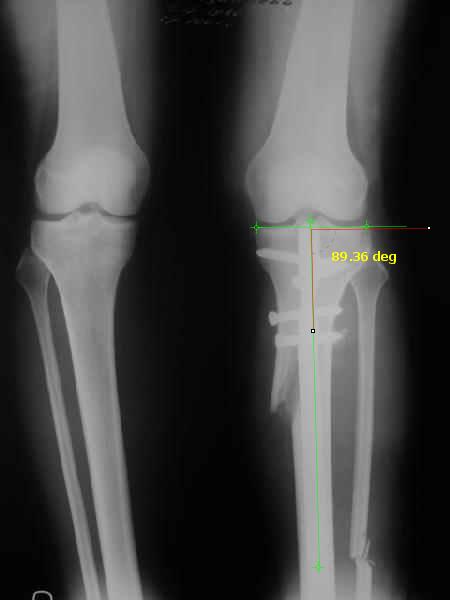

Снимки в приложении - фас сравнительный с неоперированной ногой. Жду критики.

The analysis in the attached images is direct, just using the tools.

Tibial tilt is perhaps more than you want but the tibial correction is to 90 (very slight over

correction.

Will need full length views to tell us about the hka but it appears neutral.

Measurements took 4 mins